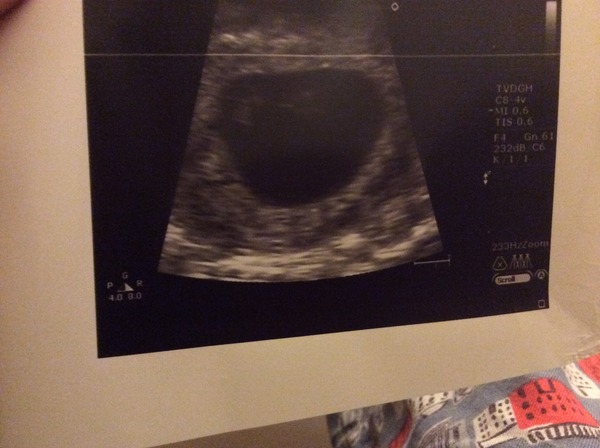

Kilicat · 21/11/2014 19:18

sdyer I've attached a photo of the photo???not the best quality! Little bean is at the top left (it was pretty amazing to see its tiny heart beating in the screen) and I think the blob in the middle is the hematoma! Have you got yours?

Kilicat your little bean!! Grin

Aaah killi ?? how far along are you?